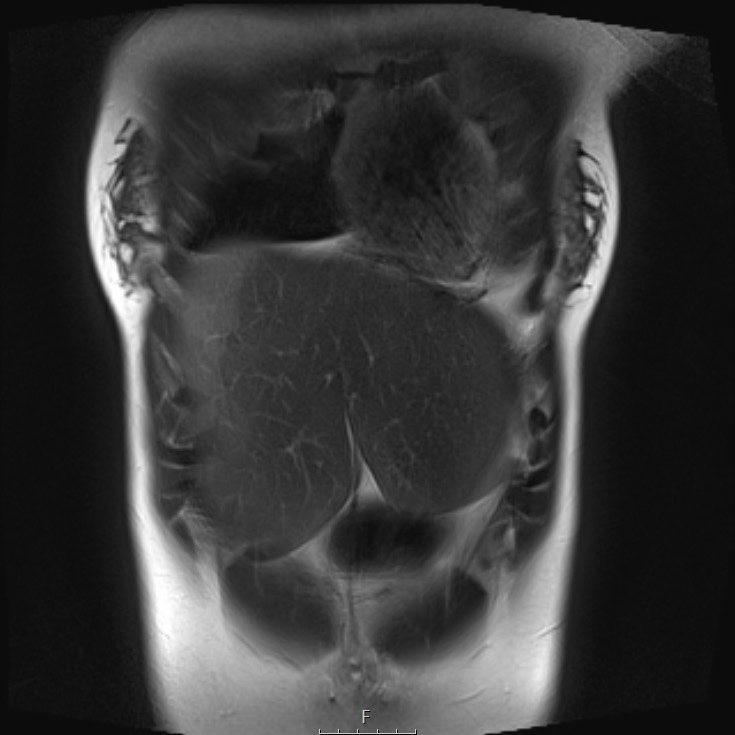

Cuộn qua chuỗi ảnh T2 theo mặt phẳng coronal.

Nghiên cứu các hình ảnh và sau đó tiếp tục đọc.

The findings are:

- Mass with encasement of the aorta and splanchnic vessels.

- Lan rộng dọc theo cột sống ngực nhưng không xâm lấn vào ống sống.

- Small liver metastases.

- Left supraclavicular mass.